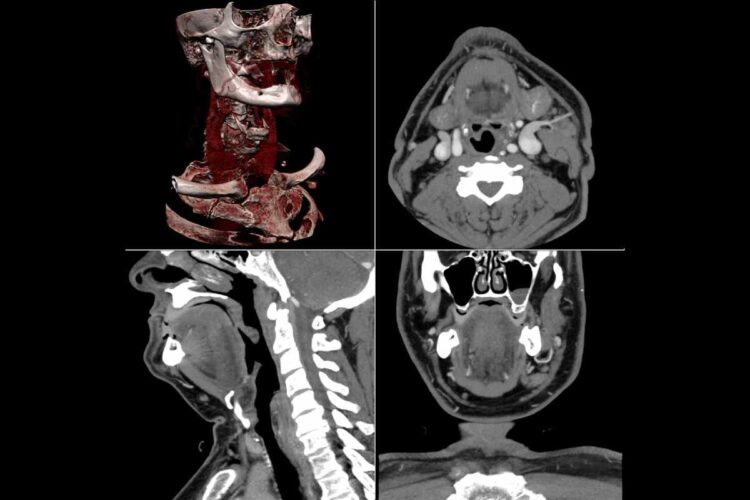

La sanità abruzzese compie un ulteriore passo verso la digitalizzazione. A breve, infatti, chi utilizza l’app Abruzzo Sanità OnLine potrà ricevere direttamente sul proprio smartphone anche le immagini diagnostiche, evitando spostamenti inutili e risparmiando tempo. La novità, su cui la Regione lavora da mesi, sarà operativa dopo l’estate e si aggiunge alle funzionalità già attive sulla piattaforma digitale.

Secondo Riccardo Urbani, consulente tecnico del presidente Marsilio, negli ultimi cinque anni l’Abruzzo ha compiuto un balzo in avanti in termini di innovazione tecnologica. “Oggi i cittadini possono prenotare prestazioni sanitarie dal proprio telefono e ricevere immediatamente referti e, a breve, anche le immagini diagnostiche. Grazie al nuovo progetto VNA (Vendor Neutral Archive), siamo la prima regione in Italia a permettere l’accesso a questi dati da qualunque struttura sanitaria”. È inoltre stato avviato un progetto di telemedicina, pensato per aiutare i pazienti con difficoltà motorie e contribuire a ridurre i tempi di attesa per le prestazioni.